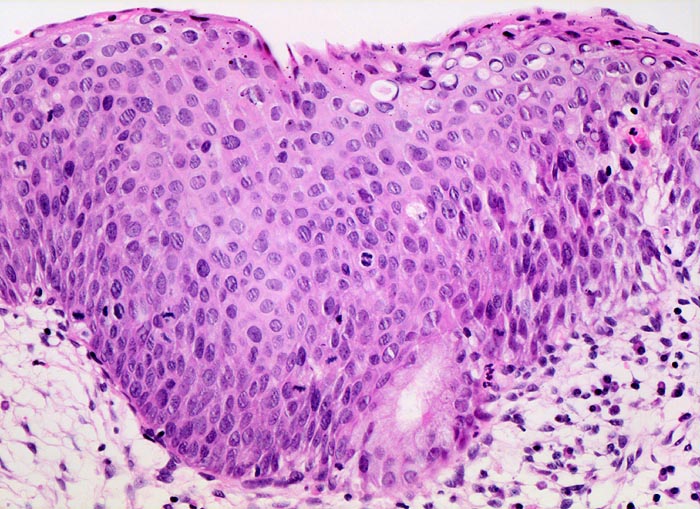

HSIL: mittelschwere Dysplasie des Plattenepithels

Die mittelschwere Dysplasie, die schwere Dysplasie und das Carcinoma in situ werden in der Bethesda Klassifikation eingeteilt als high grade squamous intraepithelial lesion (HSIL). Die zytoplasmatische Ausreifung der mässig dysplastischen Zellen entspricht dem Intermediär- bis Parabasalzelltyp. Die Kerne sind grösser als bei der leichten Dysplasie und stärker anfärbbar. Die Entrundung ist ebenfalls stärker ausgeprägt und häufiger vorhanden. Das Kernchromatin ist leicht bis mässig vergröbert und noch regelmässig verteilt. Einzelne Chromozentren können vorkommen. Die Kernmembran ist gelegentlich eingekerbt.